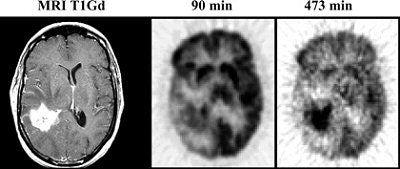

![]() |

| A 45-year-old woman with a recurrent right temporal glioblastoma multiforme shown on T1-weighted gadolinium-enhanced (T1Gd) MRI. Note the much more prominent tumor to gray matter (T/G) delineation at the later time point, 473 min compared to 90 min. Reprinted by permission of the Society of Nuclear Medicine from Spence AM, Muzi M, Mankoff DA, et al, "18-FDG PET of Gliomas at Delayed Intervals; Improved Distinction Between Tumor and Normal Gray Matter" (J Nucl Med 2004; 45: 1653-1659, p. 1655 [Figure 2]). |